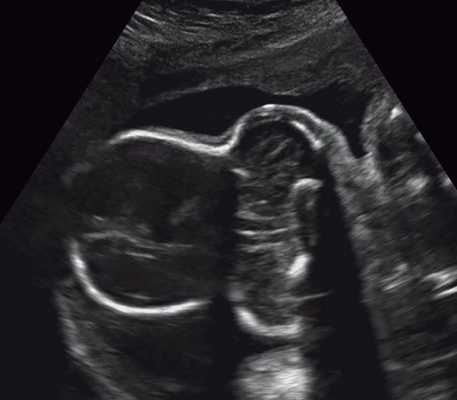

в) Изогнутая и укороченная бедренная кость.

г) Изогнутая и укороченная бедренная кость.

| Набл. 1. 24,3 нед. | БПР - 25,3 нед. ОГ - 24,6 нед. Аномально повышенная бороздчатость и выпуклость извилин нижнемедиальной поверхности височных долей (рис. 1а). | Торакоабдоминальное соотношение - 66,7% (рис. 1б) Длина ребра - среднее для 16 нед. | Бедренная кость 19,6 мм (47,8% от должной), изогнута ("телефонная трубка") (рис. 1в). Остальные кости - среднее для 15 нед. | Уплощенные тела поясничных позвонков. |

| Набл. 2. 20,3 нед. | БПР - 21,5 нед. ОГ - 20,3 нед. Уплощенный затылок. Выпуклые темпоральные бугры (рис. 2а). Аномально повышенная бороздчатость и выпуклость извилин нижнемедиальной поверхности височных долей (рис. 2б). | Торакоабдоминальное соотношение - 63,3% (рис. 2в) Окружность груди - среднее для 18 нед. Длина ребра - среднее для 15 нед. | Бедренная кость 17,7% (61% от должной), изогнута ("телефонная трубка") (рис. 2г). Остальные кости - среднее для 13-14 нед. | Гипоплазия костей носа. |

В наблюдениях 1-3 наличие изогнутой бедренной кости (по типу "телефонной трубки") (рис. 1в, 2г, 3г) позволяло предположить наличие ТД I типа. Целе направ ленное исследование головного мозга этих плодов в дополнение к описанным скелетным признакам показало и картину ДВД. Была выявлена аномально повышенная бороздчатость и выпуклость извилин нижнемедиальной поверхности височных долей у плодов в наблюдениях 1-3 (рис. 1а, 2б, 3б). Это позволило установить диагноз ТД I типа.